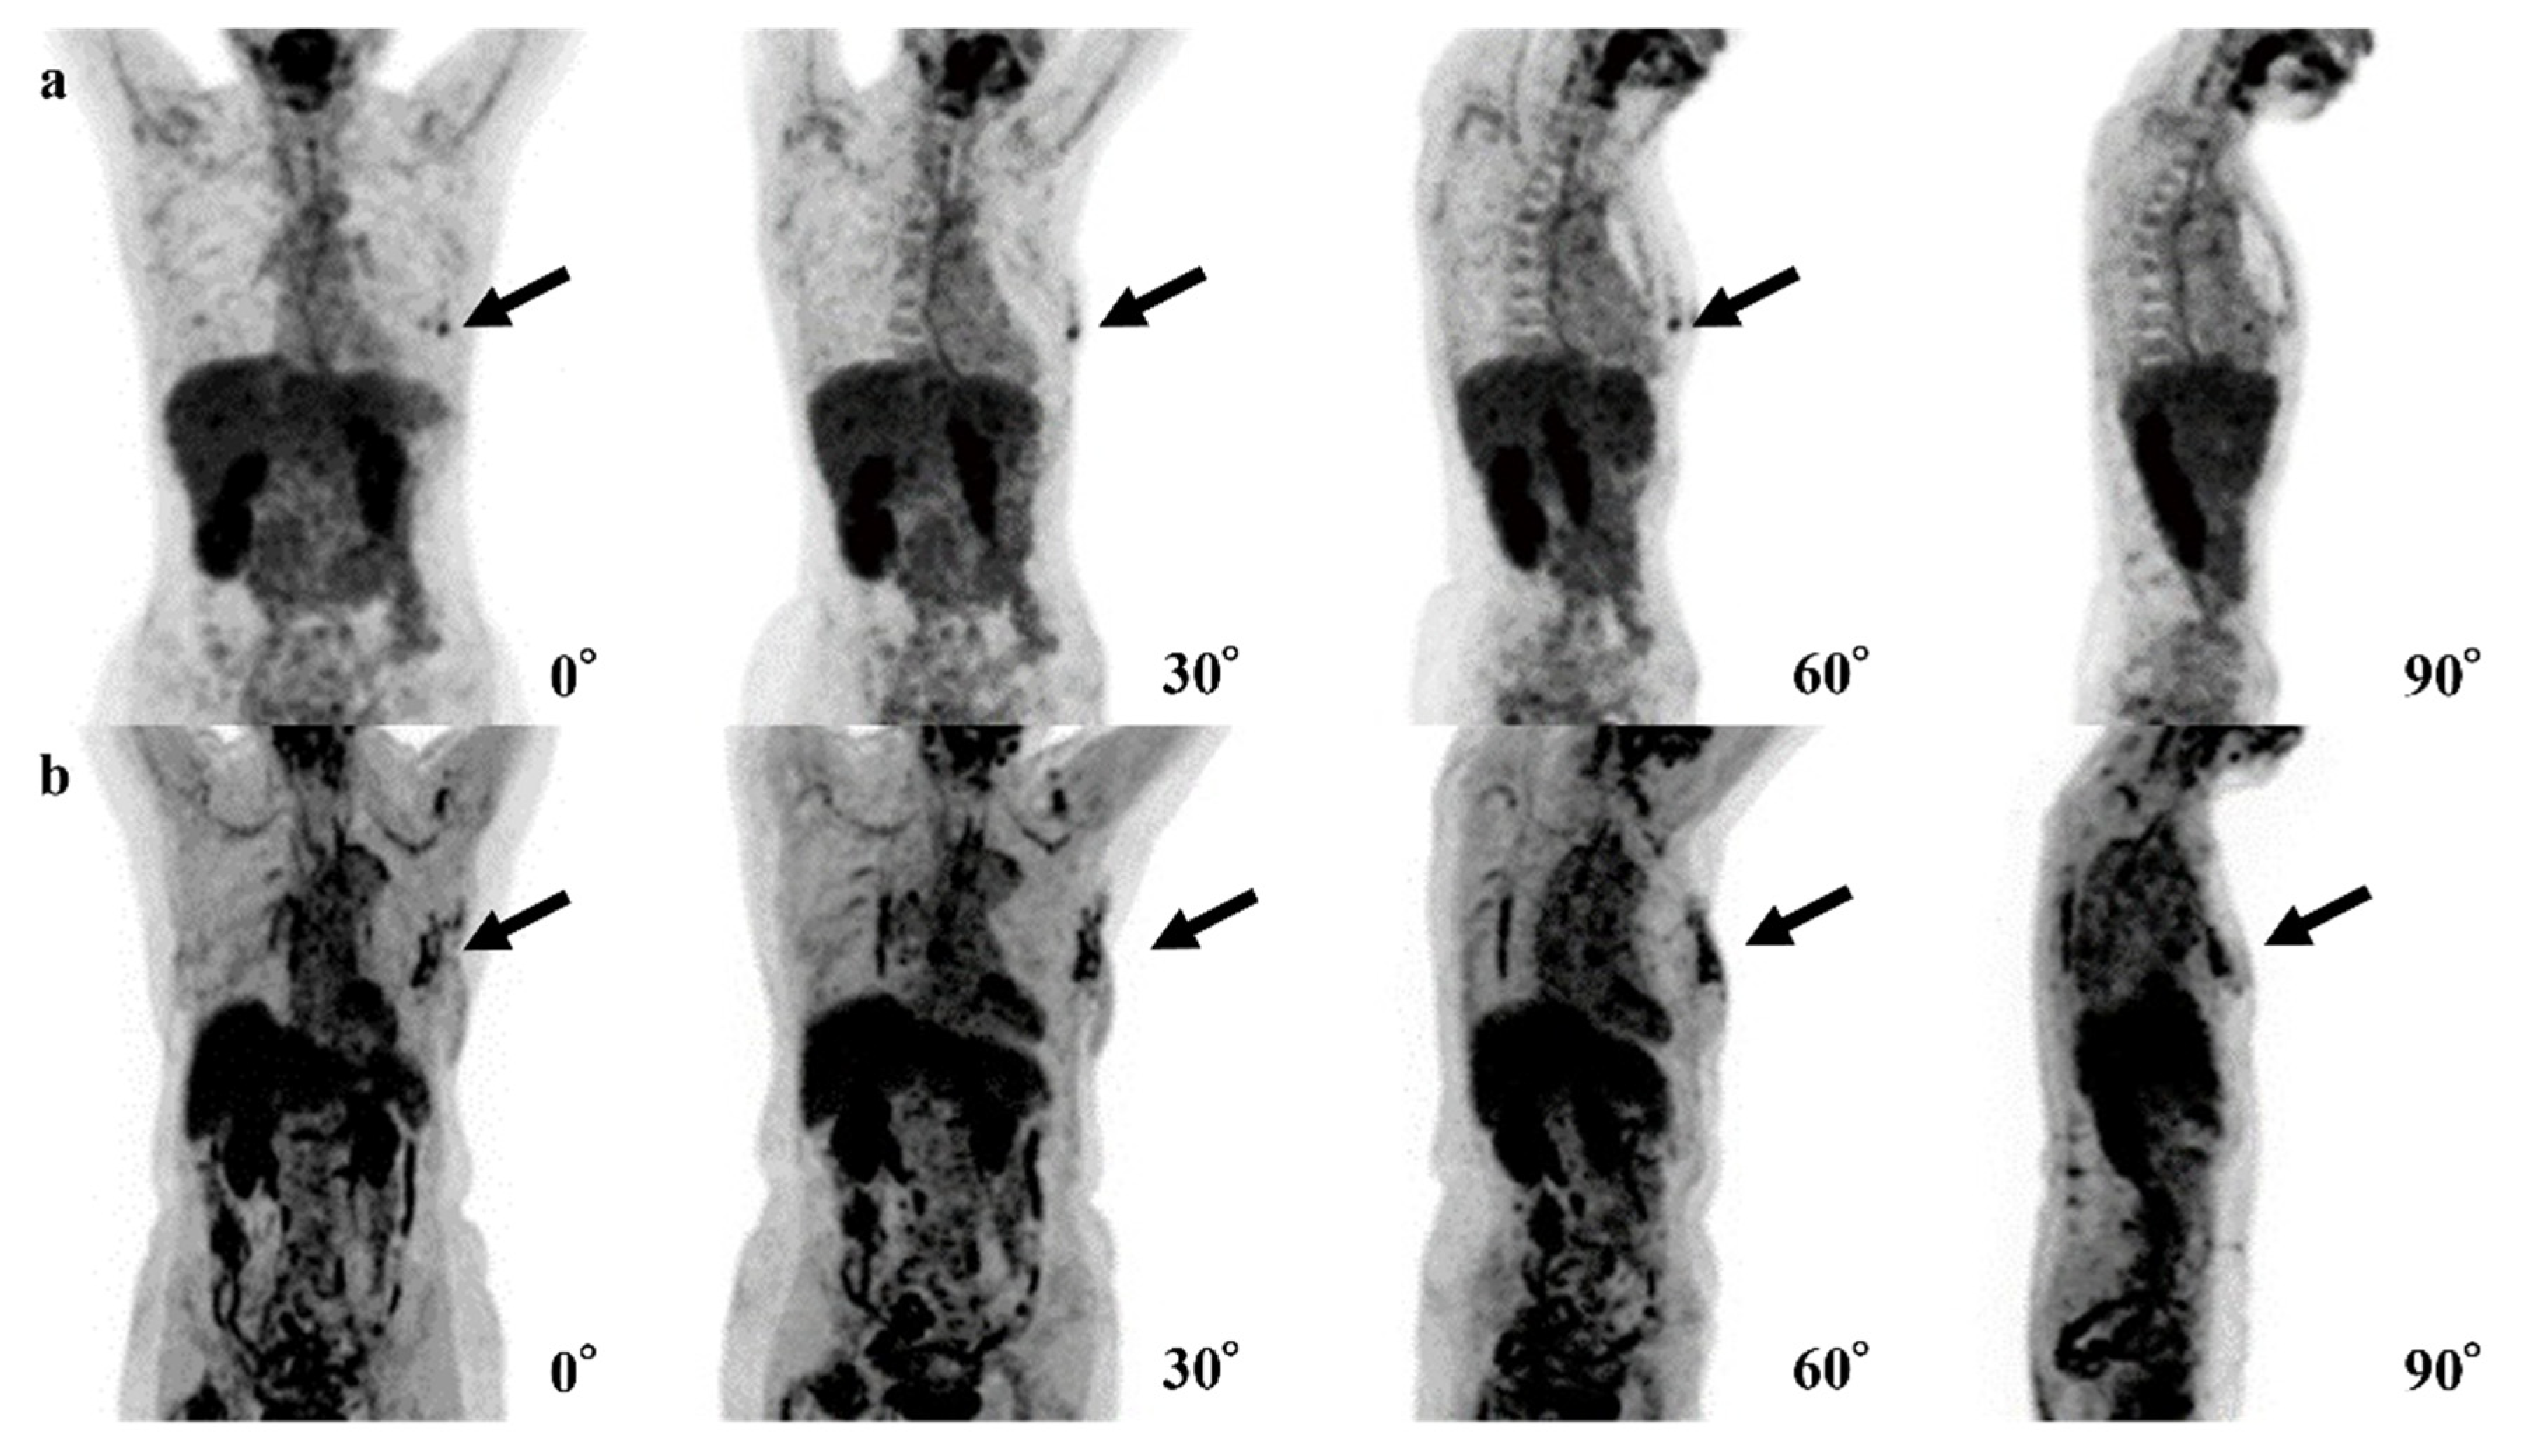

| Case | Age | SUVmax | Breast Density | Size of Invasive Components (mm) | Total Tumor Size (mm) | Pathology and Subtype | ER | PgR | HER2 | Ki67 |

|---|---|---|---|---|---|---|---|---|---|---|

| 1 | 44 | 2.0 | Heterogeneously | 11 | 11 | IDC | + | + | - | 9.1% |

| 2 | 70 | 0.9 | Scattered | None | 0.6 | DCIS | + | - | + | 15.4% |

| 3 | 70 | 1.2 | Heterogeneously | None | 8 | DCIS | + | + | + | 12.0% |